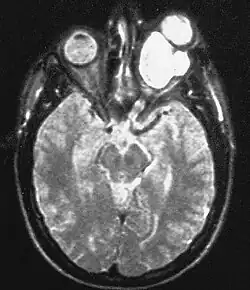

Опухоли центральной нервной системы

При нейрофиброматозе I типа частота развития опухолей центральной нервной системы составляет от 5[27] до 30 %[28][29]. Во многих случаях опухоли ЦНС у больных нейрофиброматозом не выявляются[30]. Впервые[30] взаимосвязь между нейрофиброматозом I типа и внутричерепными новообразованиями была отмечена в 1940 году[31].

Наиболее часто возникающими при данном заболевании опухолями ЦНС являются глиомы зрительных нервов, астроцитомы, эпендимомы, невриномы слухового нерва, менингиомы и нейрофибромы[32][33][34][35].

Клиническая картина при опухолях ЦНС будет зависеть от их размеров, месторасположения и вовлечённых в патологический процесс образований.